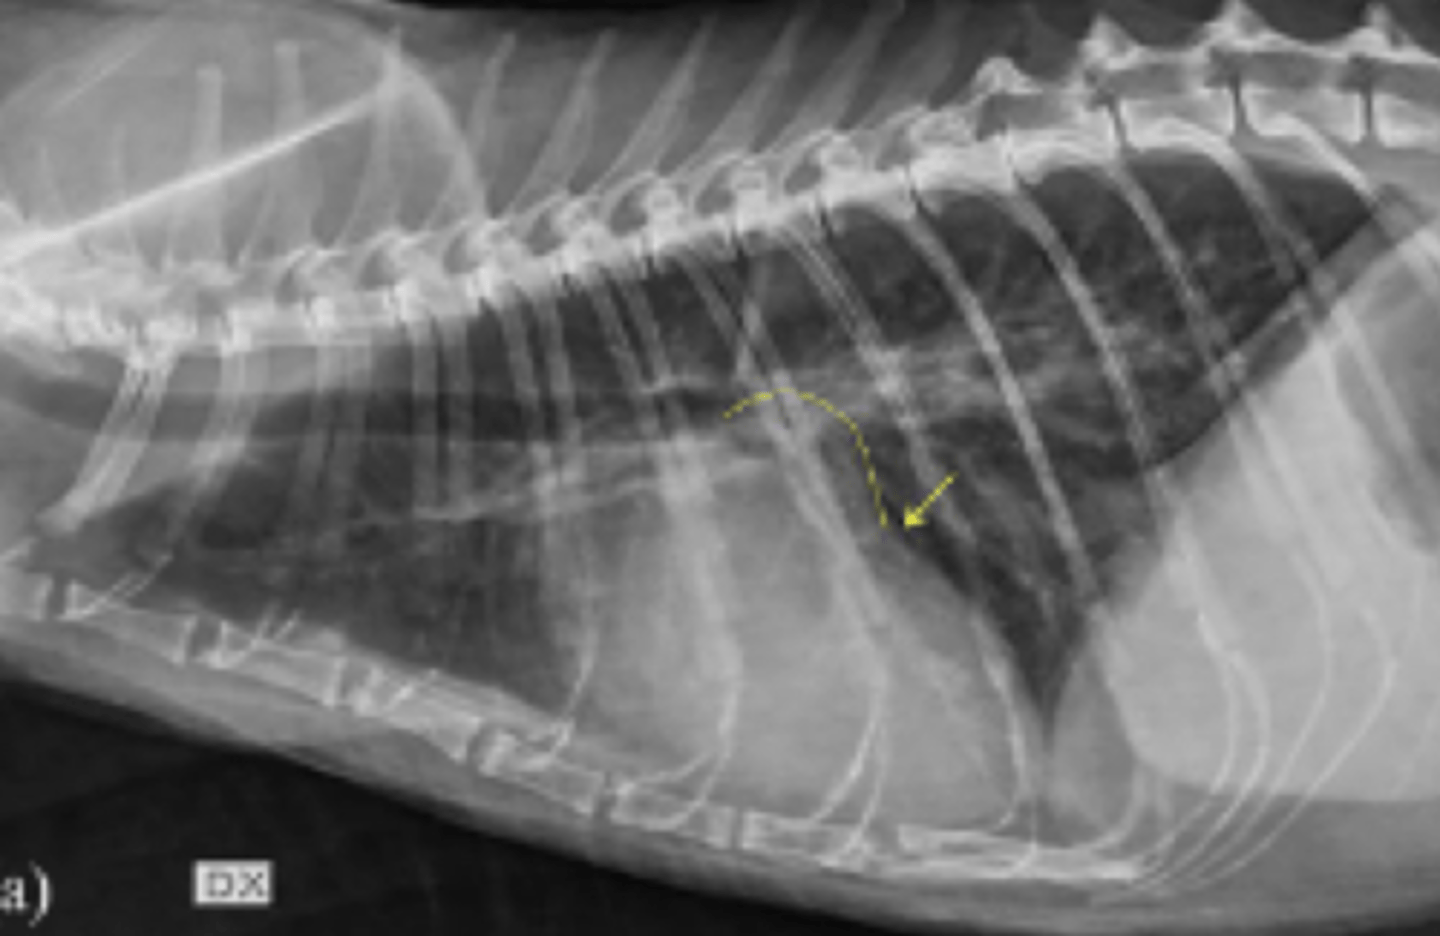

dilatación-torsión gástrica

patología: